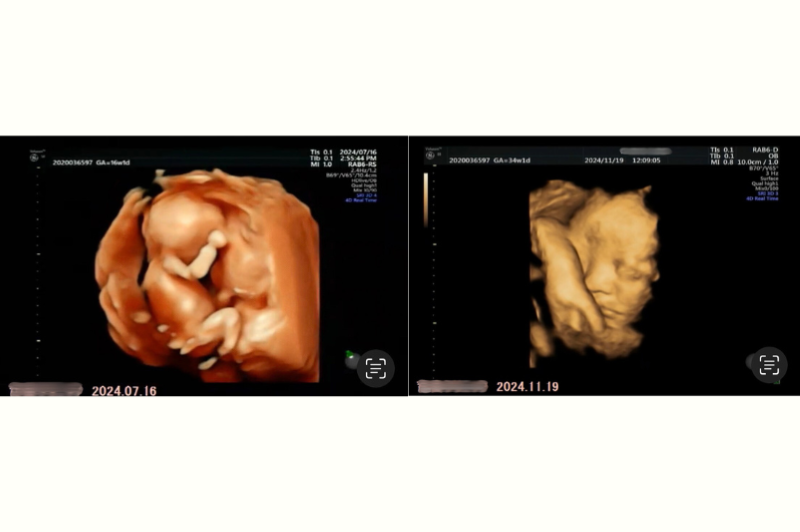

左が妊娠16週と1日、右が34週と1日のおなかの中の娘の様子です。